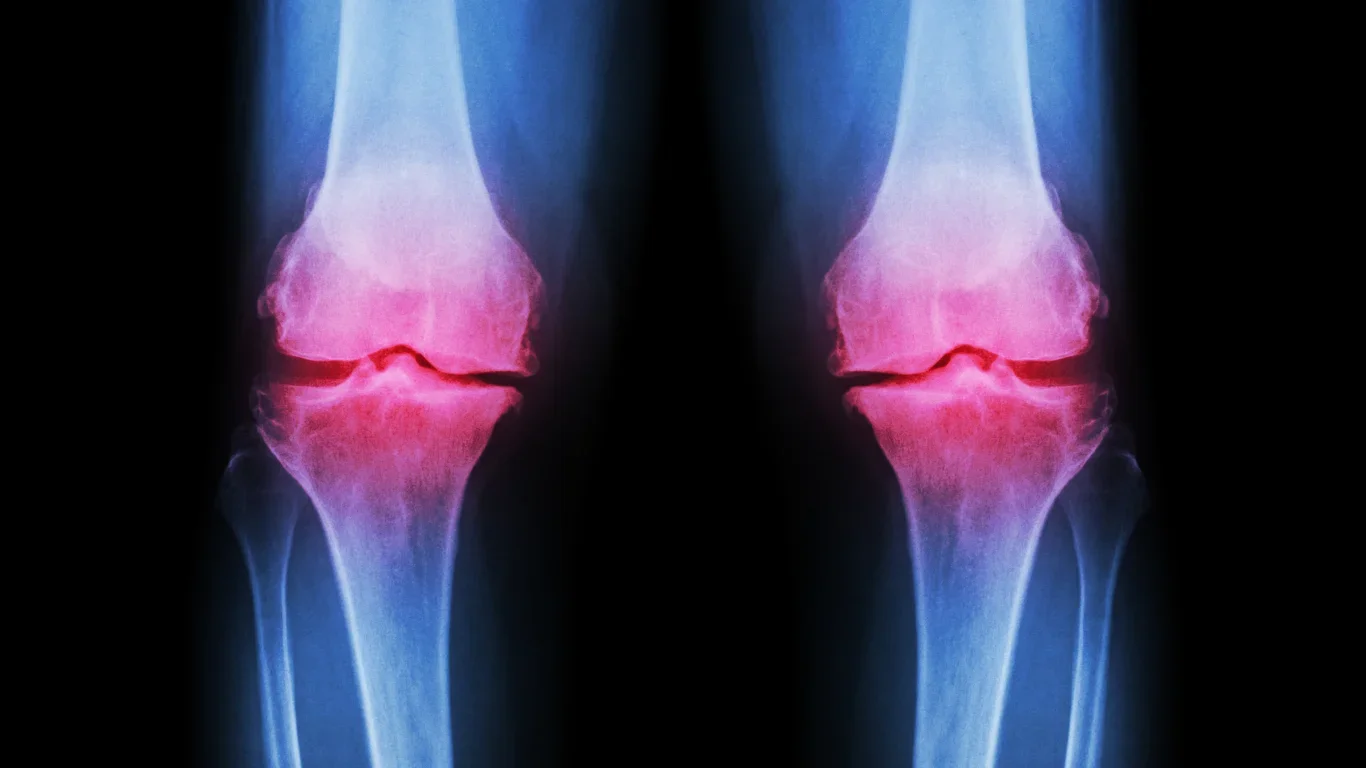

Effectiveness of Hyaluronic Acid, Platelet-Rich Plasma, and Polyacrylamide Hydrogel Injections for Knee Osteoarthritis: a Comparative Prospective Cohort Study

This study evaluates hyaluronic acid, PRP, and Arthrosamid injections for knee osteoarthritis, tracking pain, stiffness, function, and safety over time. It also examines which patients respond best, aiming to provide insight into the long-term effectiveness of these common injection therapies.

Arthrosamid vs Hyaluronic Acid vs Placebo Injection in Moderate to Severe Knee Osteoarthritis: a Randomized Controlled Trial

This triple-blind randomized trial compares polyacrylamide hydrogel (Arthrosamid) to hyaluronic acid and placebo for knee osteoarthritis. PAH is a long-lasting, non-biodegradable injectable with a strong safety record. The study evaluates pain relief, function, and safety to guide clinicians in selecting the most effective treatment for knee OA.

Comprehensive Osteoarthritis Care: Effectiveness of Knee Injections

Comprehensive knee osteoarthritis care combines education, exercise, therapy, medication, and injections. Evidence for viscosupplementation and PRP injections remains limited, highlighting the need for further research to help physicians understand patient responses and optimize treatment within a full OA management plan.